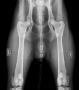

HD AA ED 00